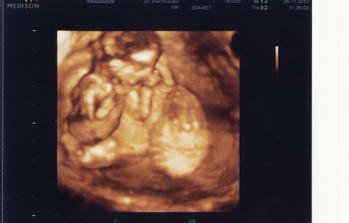

25.11. Na kontrole vše v pořádku. U ultrazvuku byl i budoucí tatínek a malý se náležitě předvedl. Vypadá to, že bude dělat Break dance 🙂 Má všechno, co mít má. Pan doktor nám sám od sebe ukázal i 3D UZ a vytiskl fotečku. Manžel sám od sebe jel nakoupit dětské oblečení a užíval si to málem více než já. Je krásné vidět, jak se na prcka těší. A viděli jsme camfrlika (výraz gynekologa) mezi nožkami 🙂